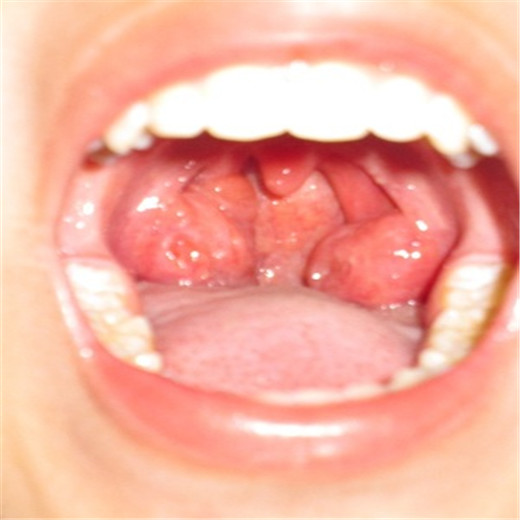

扁桃體炎圖片

扁桃體腫大